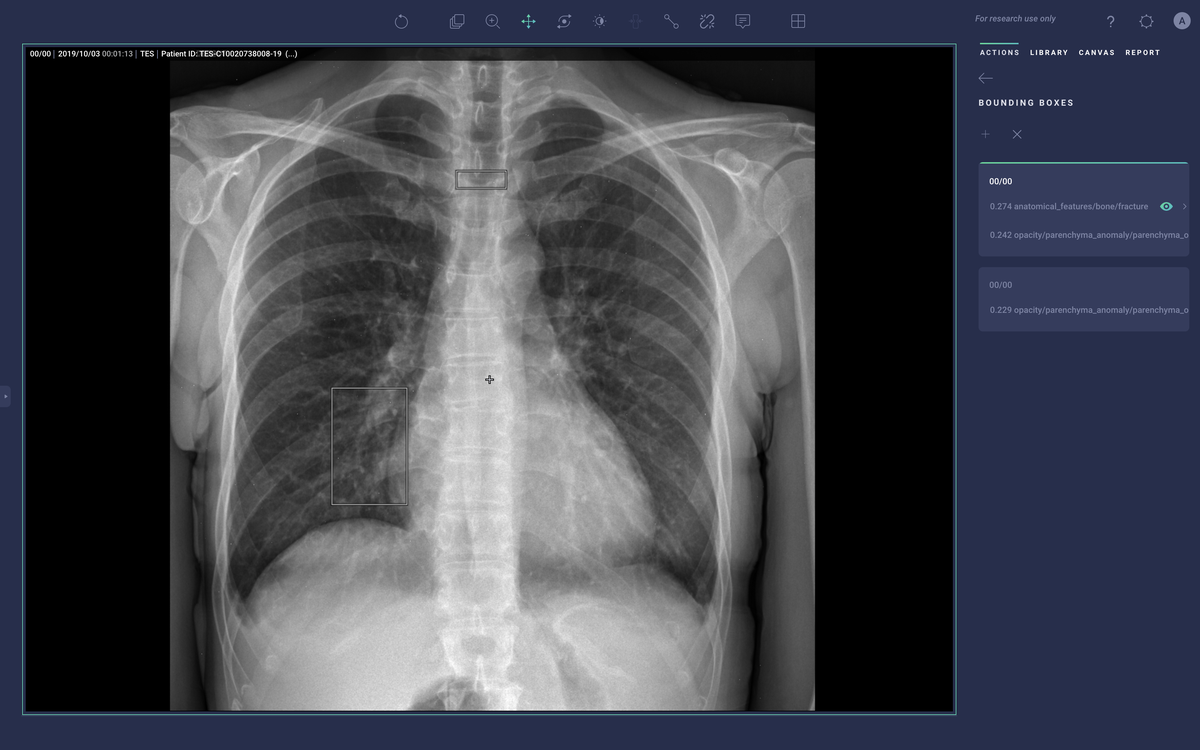

Trained on 2.5 million CXR studies, the model accepts features from qXR and considers findings indicative of COVID such as Opacities and Consolidation as well as those contra-indicative of COVID to generate a risk score of infection. Displayed prominently in the UI alongside a detailed report of the model's assessment, the score is intended to help front-line physicians or other care providers triage patients and provide guidance on treatment. In addition to the risk score, the tool also creates overlays to show where in the lungs signs of COVID may be visible, and if multiple images were acquired, is capable of tracking changes over time.

New products that have been released since Cardio DL such as Lung AI, Chest|MSK AI, and Neuro AI provide similar diagnostic support as qXR and LUnit, but couple with workflow automation that comes via integration with the Radiology Information System (RIS), PACS, electronic medical record (EMR), and dictation system. They process DICOM data to generate labels, annotations, heatmaps, and bounding boxes around regions of suspected illness. They then push those labels into the medical IT infrastructure to help prioritize the review of studies that may have abnormal findings and emphasize aspects of the study that may be concerning.